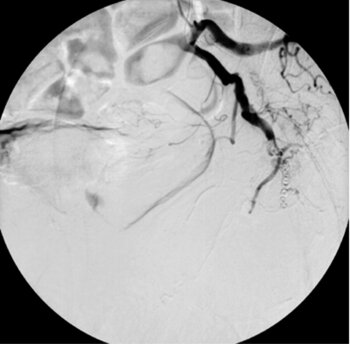

Fallbeispiele Leber – Spiralembolisation von blutenden Lebermetastasen

CT des Oberbauchs: Multiple zystische Lebermetastasen eines Klarzellsarkoms mit aktiver Blutung im Segment 6. Mehrere Blut-Flüssigkeitsspiegel in den zystischen Metastasen und subkapsulär.

Digitale Subtraktionsangiografie: Superselektive Sondierung und Darstellung der mutliplen Blutungsherde. Die Leberarterien werden durch die zystischen Metastasen ausgespannt.